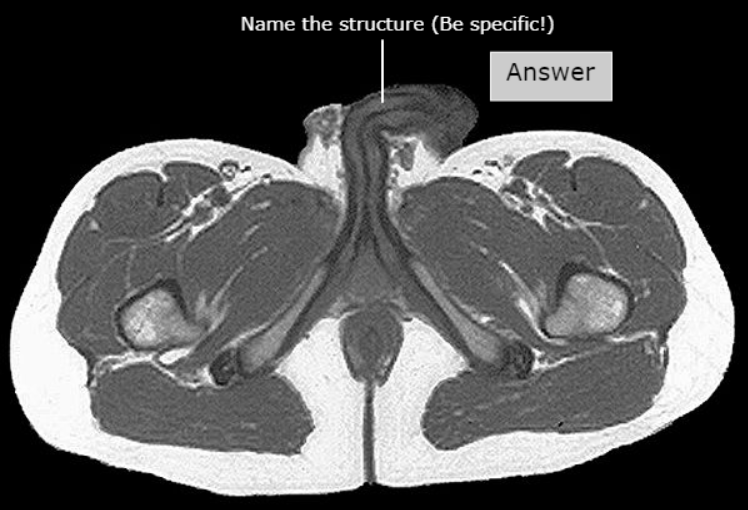

Levator ani